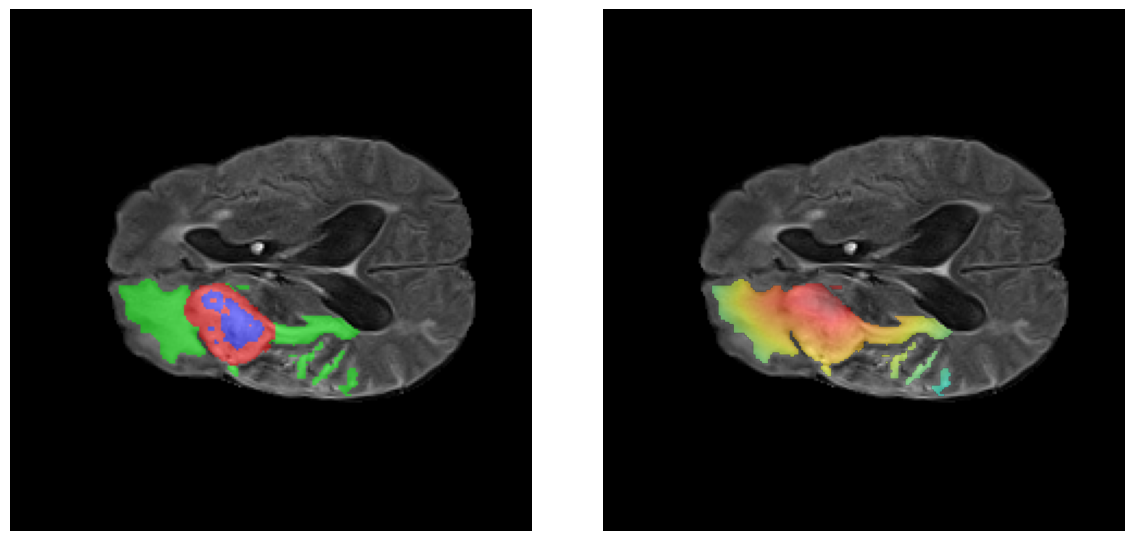

Ejemplos HGG - Atención en Núcleo Necrótico y Tumor Realzado

HGG Grad-CAM++ 1 HGG Grad-CAM++ 2 HGG Grad-CAM++ 3 HGG Grad-CAM++ 4 HGG Grad-CAM++ 5 HGG Grad-CAM++ 6

Los heatmaps muestran que el modelo concentra su atención en las regiones de Tumor Realzado (rojo) y Núcleo Necrótico (azul), características patológicas clave de los gliomas de alto grado.

Ejemplos LGG - Atención Difusa en Edema Peritumoral

LGG Grad-CAM++ 1 LGG Grad-CAM++ 2 LGG Grad-CAM++ 3 LGG Grad-CAM++ 4 LGG Grad-CAM++ 5 LGG Grad-CAM++ 6

Para casos LGG, la atención del modelo es más difusa y se concentra principalmente en la región de Edema Peritumoral (verde), consistente con la naturaleza más infiltrativa y menos agresiva de estos tumores.

El análisis Grad-CAM++ reveló que el modelo desarrolla automáticamente la capacidad de localizar las regiones tumorales. Para casos HGG, la atención se alinea fuertemente con las regiones de Tumor Realzado (ET) y Núcleo Necrótico (NCR). En contraste, los casos LGG muestran atención más difusa, principalmente concentrada en la región de Edema Peritumoral (ED), lo cual es consistente con la patofisiología conocida de los gliomas.